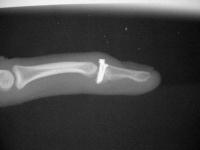

Intraoperative fluoros: The injury, reconstruction through a bayonette exposure, stable reduction.

Provisional fixation with Kwires through extensor tendon

Replace Kwires with screws